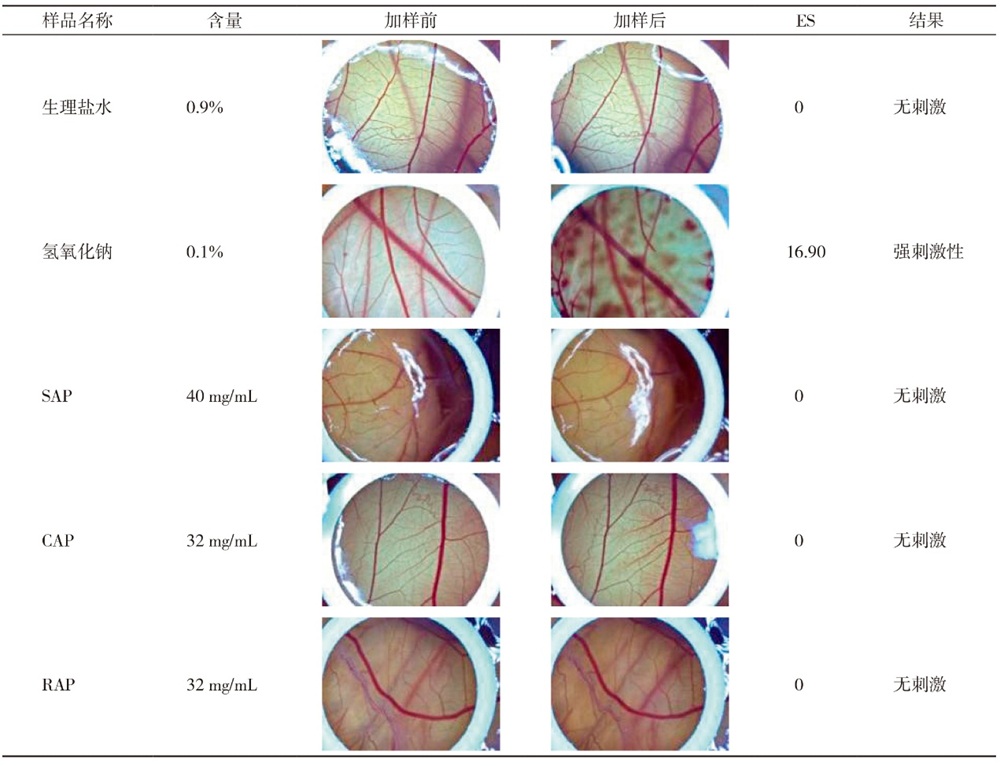

国家认证认可监督管理委员会. 化妆品眼刺激性/腐蚀性的鸡胚绒毛尿囊膜试验: SN/T 2329—2009[S]. 北京: 国家质量监督检验检疫总局, 2009.